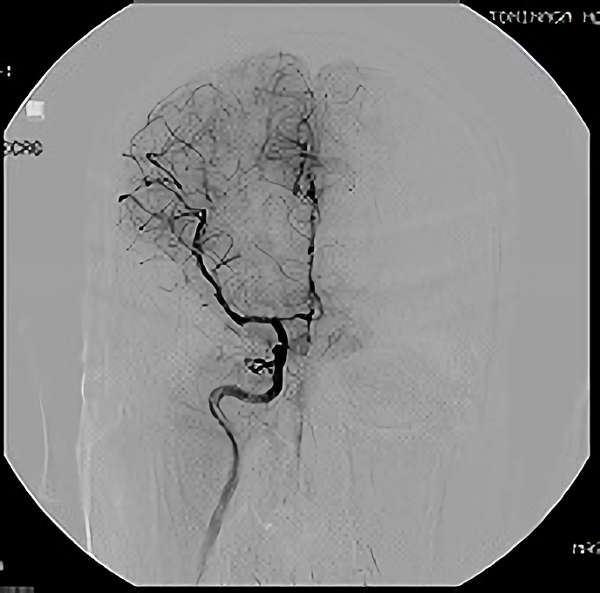

No.452 手術後

全治。

脳血管撮影により完全除去が確認された